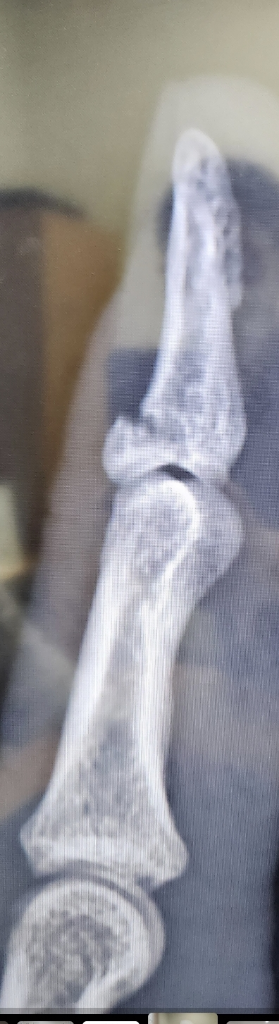

왼쪽검지손가락 골절 수술안하면 안될까요?

왼쪽 검지 첫마디가 골절되었네요

혹시 수술없이 깁스치료로는 안좋을까요?

수술이 필수인지...........

• 1번 째 사진

관절부분이기 때문에 수술적 치료가 필수입니다.

단순 깁스만으로는 골유합이 제대로 되지 않을 수 있고 추후 관절염 등이 발생할 가능성도 높습니다.

증상의 정도가 심하거나 질문자님의 경우처럼 골편의 크기가 큰 경우에는 수술이 필요합니다.